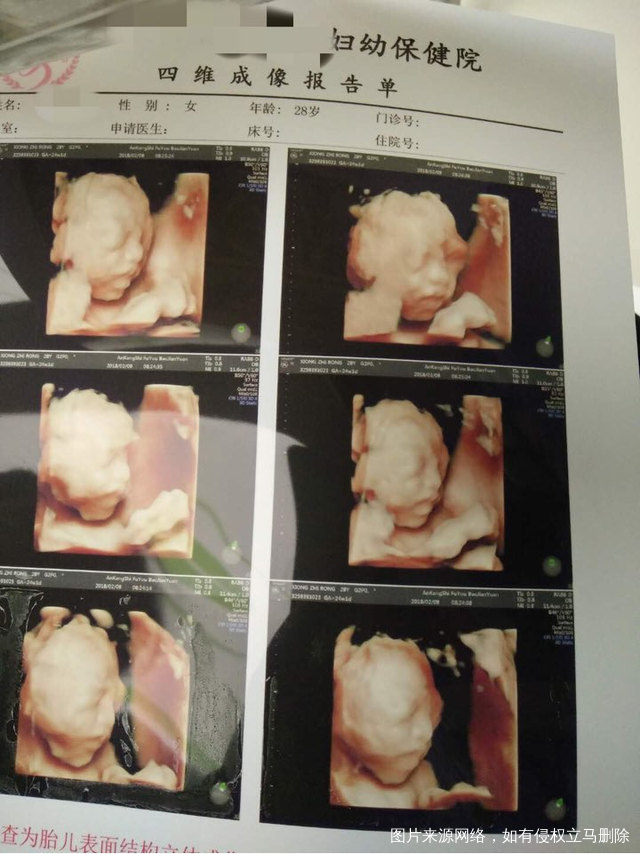

最近才做的四维,请医生帮我看看一切都正常吗?胎儿大小咋样?